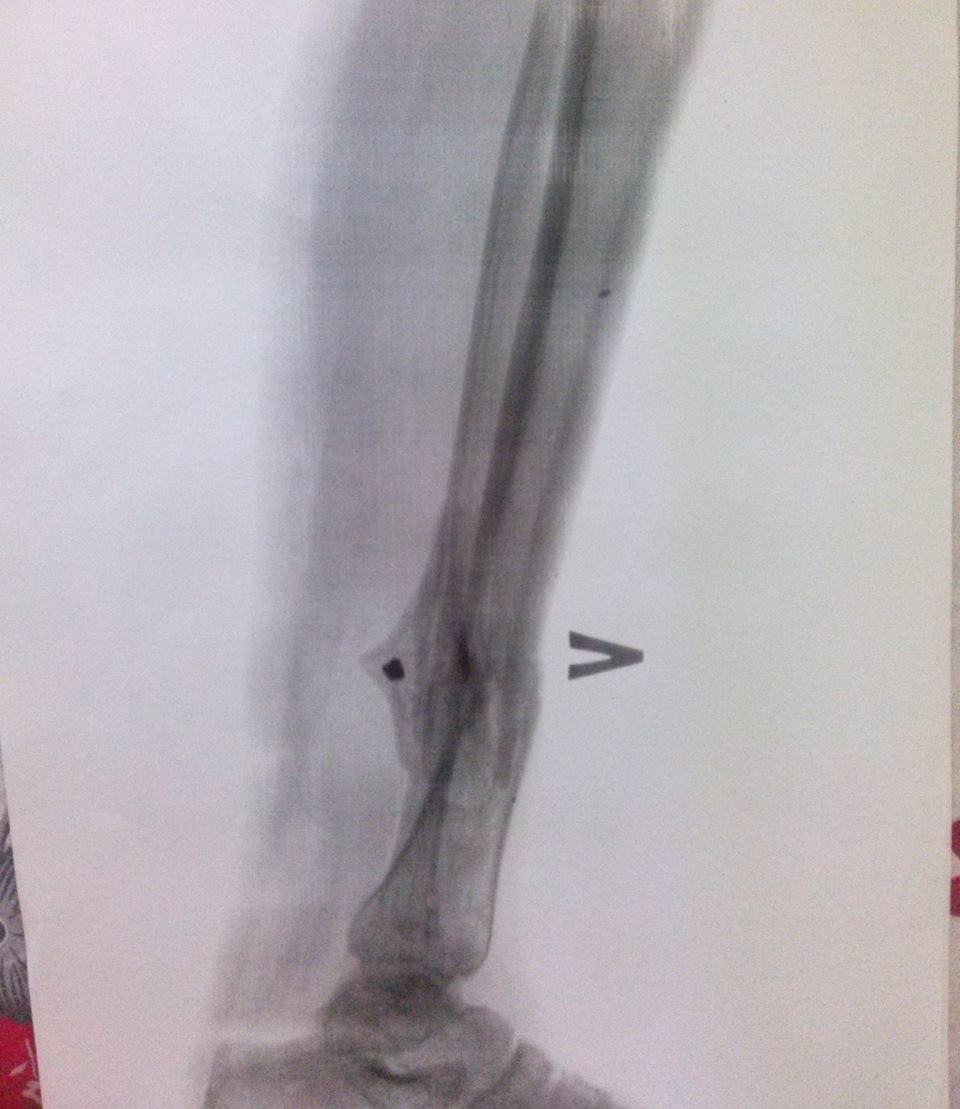

Рентгенограмма выявила:

- перелом левой голени в средней трети с костным дефектом и смещением отломков;

- перелом пяточного бугра и ладьевидной кости без смещения отломков.

Открытый перелом обеих костей левой голени в средней трети с дефектом костной ткани и смещением отломков. Открытый перелом пяточной бугра левой пяточной кости и ладьевидной кости без смещения отломков. Обширная рваная рана левой голени. Рваная рана левой стопы. Травматический шок I степени (лёгкий).